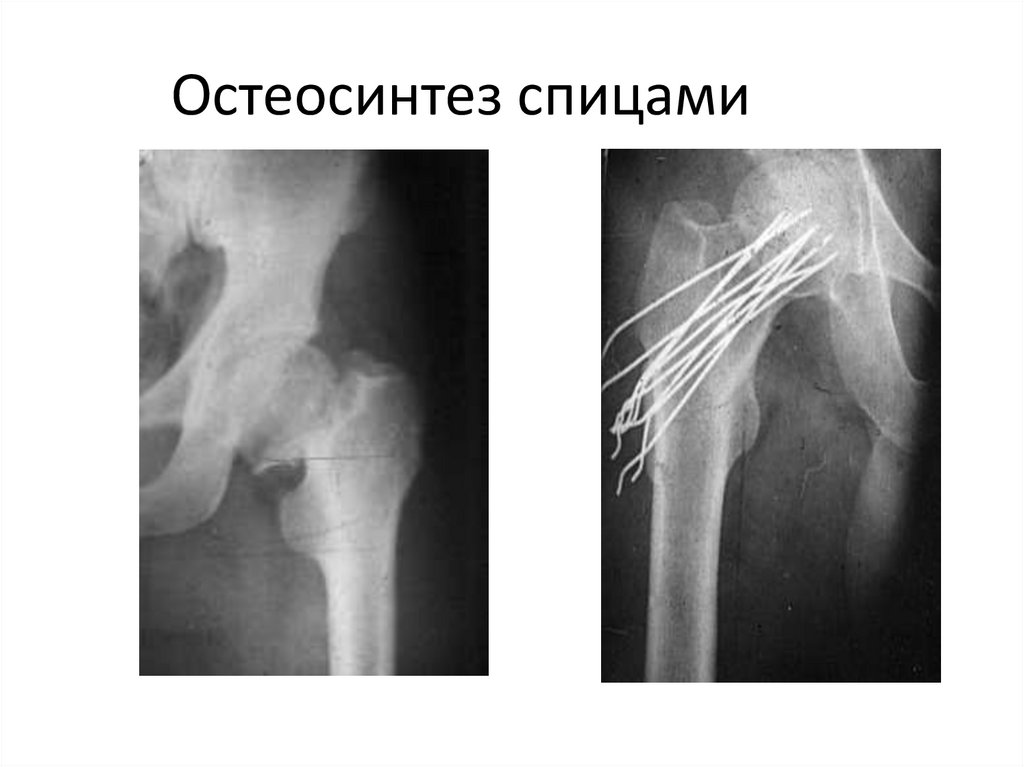

Остеосинтез спицами

81.